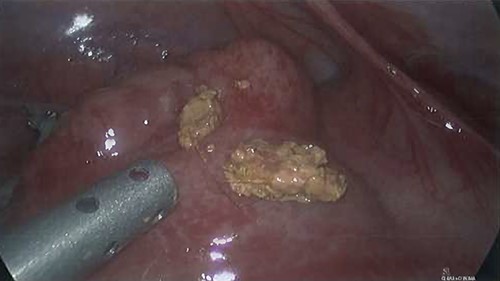

The patient proceeded to laparoscopic appendicectomy. At the outset of the procedure a cluster of short, firm, light coloured hairs were removed from the umbilicus. These hairs were different to the patient’s own and appeared like animal hair. Intra-operatively, the appendix was found to be inflamed with a perforated base (Fig. 3). Faecoliths, containing a large volume of hairs identical to those found in the umbilicus, had escaped the appendix through the perforation (Fig. 4). Pus was identified in all four quadrants of the abdomen. After dissection of the meso-appendix, a partial caecectomy was performed using a laparoscopic stapler. The hairs were carefully removed, and the abdomen was irrigated. A drain was placed in the pelvis.